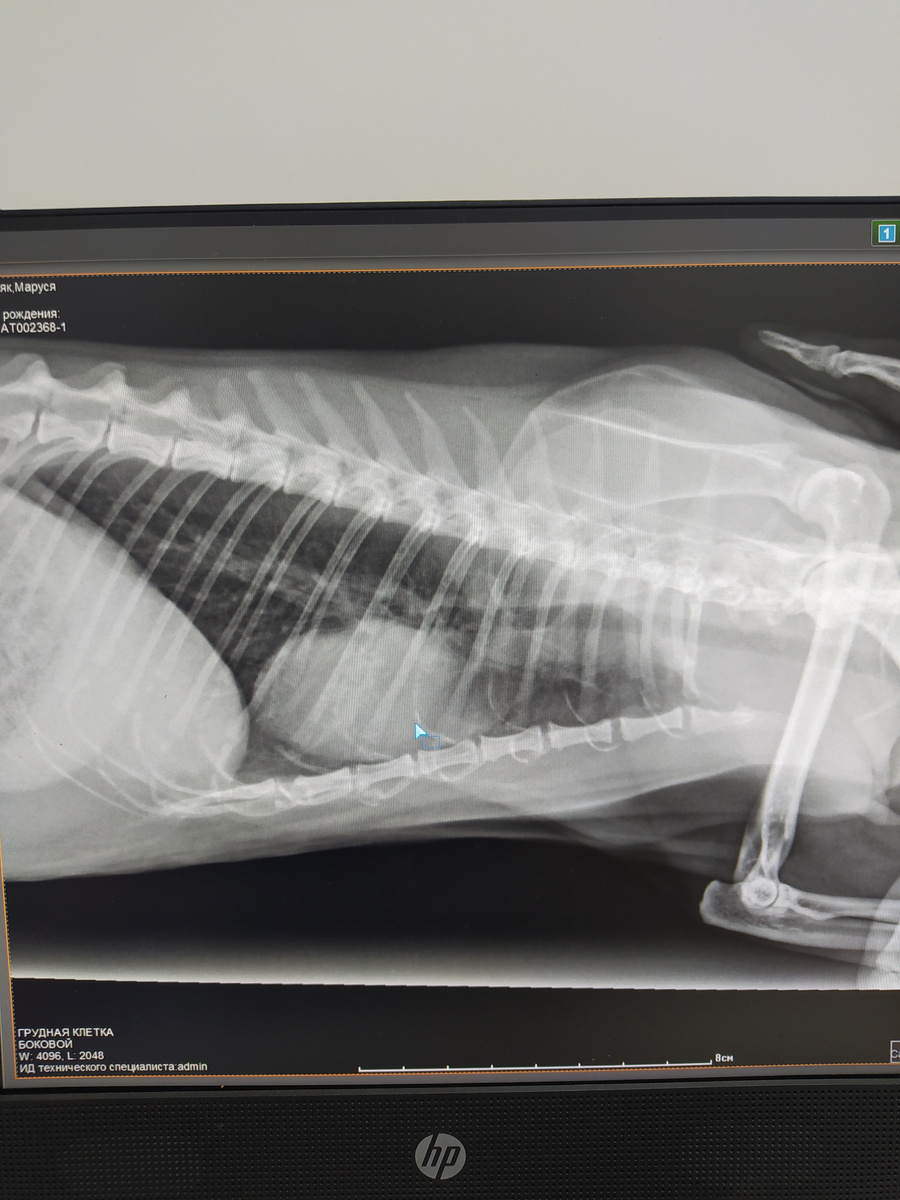

Образование в проекции сердца

• Рентгенография (рентген) грудной клетки. Это золотой стандарт диагностики кашля. Снимки делают в двух проекциях (прямой и боковой). Рентген позволяет оценить:

Легкие: Признаки пневмонии, отека, опухолей, бронхита (утолщение стенок бронхов – «симптом трамвайных рельсов»).

Сердце: Размер, форму, наличие признаков застоя.

Трахею: Признаки коллапса.

Плевральную полость: Наличие жидкости или воздуха.